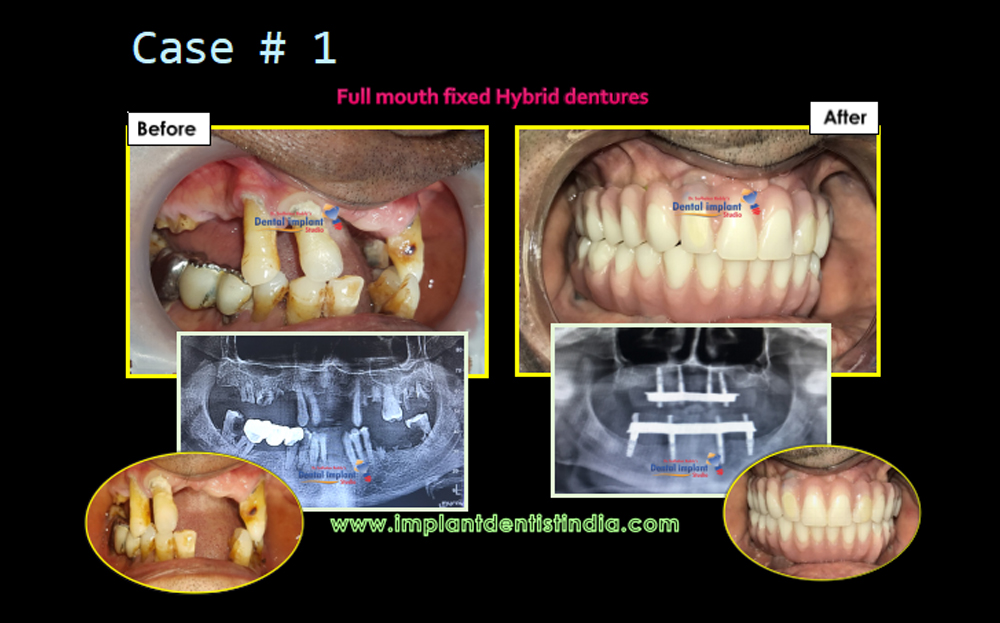

Full Fixed Dentures (Hybrid Dentures) | View Case Series